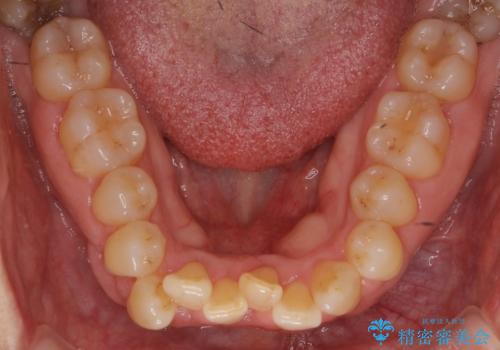

- 前歯のがたつきを主訴に来院。

右下の犬歯が歯ぐきが痩せて、歯肉退縮しておりそれを抜歯しました。

右下の犬歯の1本抜歯で最小限の抜歯で並べることができました。

奥歯も上下交互になるようにかみ合わせることができました。